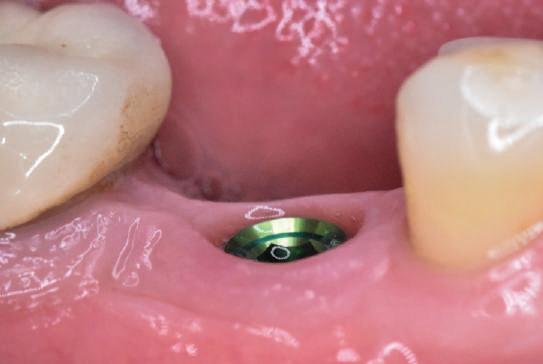

10. S-a conectat un bont de vindecare, iar lambourile au fost suturate cu fire resorbabile 4-0.

tat un bont de vindecare și lambourile s-au suturat cu fire resorbabile 4-0 (fig. 10).

Scanarea intraorală finală și procedurile de restaurare au fost finalizate 3 luni mai târziu, iar implantul se afla în funcțiune de 36 luni la momentul redactării prezentului articol.